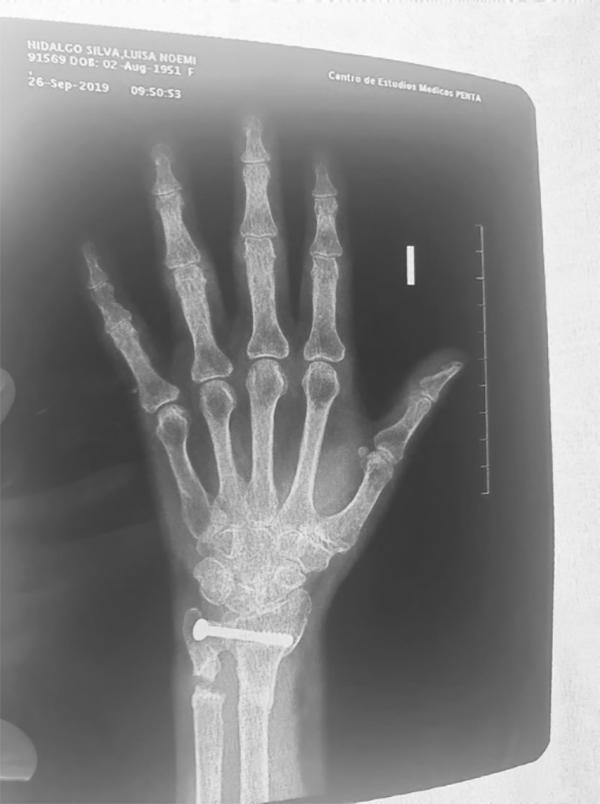

Todos fueron estudiados mediante el test clínico de Kakamura y un par radiográfico de muñeca (fig. 1). Este test se realiza con el codo del paciente apoyado en un escritorio mientras el médico toma firmemente con una mano el radio del paciente y con la otra mano imprime movimientos de traslación volar y dorsal en pronación, supinación y posición neutra.1-3

Figura 1: Radiografía de muñeca izquierda con artrosis de la articulación radiocubital distal.

Evaluamos la varianza cubital radiográficamente, la configuración articular, el pinzamiento bajo carga y el desgaste articular. La varianza debe evaluarse en pronosupinación neutra y en pronación máxima, donde aumenta 1-2 mm.2, 3